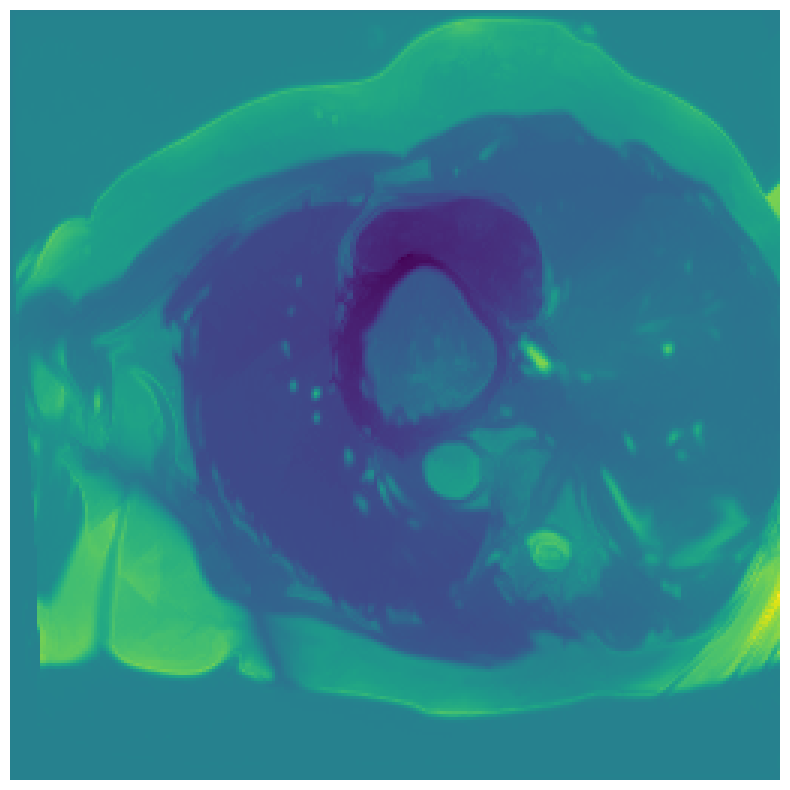

We normalize the volumes and resize the slices to pixels. As the official dataset comes with full annotations, we create a synthetic point ground truth. This is done by first randomly choosing the centers of the point annotations within the class masks, followed by filling an ellipse with axes lengths of and (in pixels) around each center. The intersections of these elliptic discs with the underlying full annotations are then used as our point ground truth. See Figure 2 for an example of the created weak annotation mask. The point annotations are created for every slice, one for each foreground object present in the slice.

5.1 Segmentation of cardiac structures

The average 3D Dice scores and HD95 values on the ACDC test set are given in Table 2, and boxplots in figures 4 and 5 show the distributions. We see that, in terms of DSC, the proposed strategy of using intensity-aware distances withing boundary loss performs better than simply using the Euclidean distance, with the best results achieved by using the strictly intensity based MBD. The HD95 however favors the original version of , which may be do to its smoother predictions and less fragmentation and oversegmentation. The CRF-loss results are significantly worse in both metrics.

In Figure 3 we show the 3D DSC validation curve evolution for a single run. The CRF-loss seems to have converged to a low DSC value, while all settings combining CE and boundary loss reach values close to the full supervision in the beginning of the training and then slowly collapse towards to the point annotations. The MBD version stands out, degrading slower, thus providing a wider range of potentially good models for evaluation.

Qualitative comparison

In Figure 6 we provide qualitative results on a number of randomly chosen test set slices. Upon visual inspection, we can observe that training with the intensity-aware distances (particularly with and ) follows the image gradients better and is better at recovering the underlying shape than the Euclidean version. The CRF-loss seems to recover the shape of the myocardium and left ventricle to some extent, but fails entirely on the right ventricle.